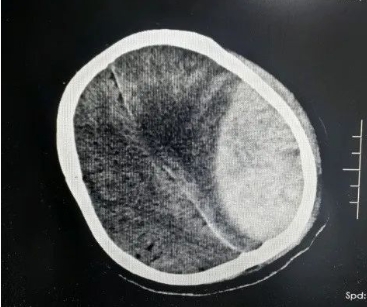

5月1日,青岛西海岸新区中医医院急诊科接诊了深度昏迷、瞳孔散大,生命体征极其微弱的宋先生。据目击者描述,其被发现时已倒在路边,生命垂危。急诊团队迅速启动抢救流程:气管插管、建立静脉通路维持生命体征,颅脑CT显示“颅骨骨折、大量硬膜外血肿、脑疝”。

外五科(神经外科)团队会诊后锁定“元凶”,神经外科最凶险的急症之一——上矢状窦破裂。上矢状窦作为颅内重要静脉窦,此处破裂出血如“洪水决堤”,极易引发脑肿胀、脑疝,死亡率超60%,且手术视野极易被汹涌出血覆盖,稍有不慎便会导致脑功能不可逆损伤,被称为神经外科“手术禁区”!

“必须分秒必争!”外五科主任侯鹏志当即联合麻醉科、输血科组建抢救团队,制定“精准止血+血肿清除”手术方案。术中“险象环生”,开颅瞬间,破裂的上矢状窦喷涌出血,患者血压骤降至52/32mmHg,麻醉团队迅速予升压药物泵入并加压输血以维持血压稳定!大量出血导致手术视野模糊,稍有不慎就可能引发“灾难性”后果,在模糊视野中主刀医师精准分离粘连组织,以毫米级操作修补窦壁、清除血肿……4小时鏖战后,出血成功控制,脑组织压迫解除,患者生命体征趋稳!